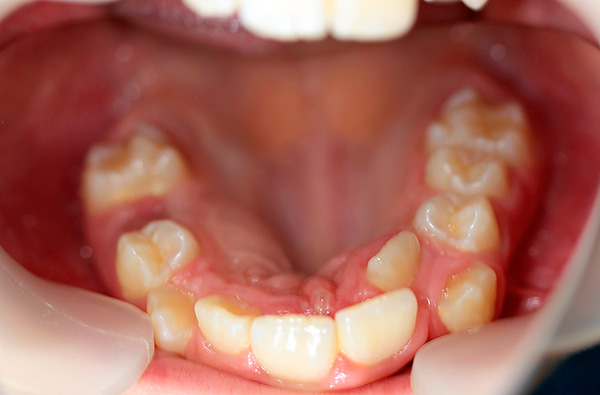

- Violações do tempo e da sequência da dentição. Cada dente deve entrar em erupção normalmente na dentição para determinar o tempo e o local especificado para esse dente. Se, por exemplo, um dente não entrar em erupção por um longo período de tempo por algum motivo, os dentes existentes geralmente se movem para preencher um vazio (compensar um defeito na dentição) - como resultado, são criados contatos patológicos, razão pela qual o desenvolvimento de uma mordida cruzada.E se os dentes entrarem em erupção muito mais tarde, quando a dentição já estiver formada, os “camaradas tardios” terão que literalmente encontrar um lugar para si. Por exemplo, um dente pode cortar as dobras transitórias das gengivas, na direção dos lábios, bochechas ou palato;

- Perda precoce de dentes decíduos. A remoção de dentes temporários devido a cárie e suas complicações muitas vezes leva à formação de uma cruz e outros tipos de mordidas anormais. Como se costuma dizer, a natureza não tolera o vazio e, se houver um espaço livre, os restantes dentes de leite o preencherão, curvando-se e se movendo em direção ao defeito, forçando outros dentes permanentes a entrar em erupção fora da dentição ou com uma inclinação ou rotação ao longo do eixo;